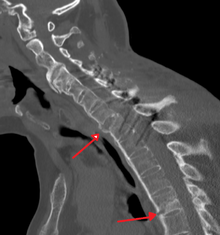

Fracture of the T5 and C7 vertebra due to trauma in a person with ankylosing spondylitis as seen on a CT scan

Prognosis is related to disease severity.[9] AS can range from mild to progressively debilitating and from medically controlled to refractory. Some cases may have times of active inflammation followed by times of remission resulting in minimal disability while others never have times of remission and have acute inflammation and pain, leading to significant disability.[9] As the disease progresses, it can cause the vertebrae and the lumbosacral joint to ossify, resulting in the fusion of the spine.[35] This places the spine in a vulnerable state because it becomes one bone, which causes it to lose its range of motion as well as putting it at risk for spinal fractures. This not only limits mobility but reduces the affected person's quality of life. Complete fusion of the spine can lead to a reduced range of motion and increased pain, as well as total joint destruction which could lead to a joint replacement.[36]